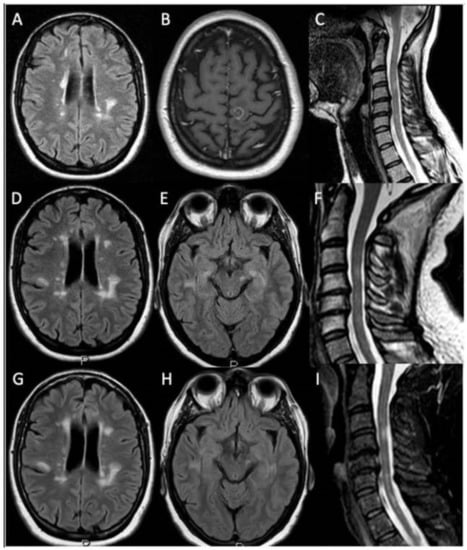

The patient’s father died from ALS and her paternal uncle had Parkinson disease (genetic test was not performed in both patients). The medical history was otherwise unremarkable, and at the time of presentation she was not taking medication other than azathioprine. In December 2017, neurological examination revealed hypotrophy of the left deltoid, the left periscapular, and the left bicep. Weakness of the following muscle was found (right/left; Medical Research Council [MRC] grades): deltoids (5/3), supraspinatus (5/4), infraspinatus (5/4), biceps (5/4−), finger extensor (5/3). Interosseous, finger flexors, wrist extensor/flexor, brachioradialis, triceps were 5/5. Tendon reflexes were (right/left): triceps (2+/0), biceps (2+/1+), brachioradialis (2+/1+), Achilles’ tendon and patellar reflex (2+/2+). We also observed mild sensory ataxia, with a positive Romberg test. A brain MRI was performed, and new demyelinating lesions were not shown (Figure 1G,H). Considering the prominent involvement of the left upper limb, a cervical MRI was performed and detailed spondylosis with posterior osteophytosis without spinal cord and nerve root compression (Figure 1I).

Figure 1. Patient’s brain and spinal cord MRIs. 1.5 tesla brain and spinal cord MRI obtained before and after IV gadolinium injection. November 2006: axial fluid-attenuated inversion recovery (FLAIR) and t2 weighted sequences showed the presence of multiple demyelinating lesions located in the periventricular and hemispheric deep white matter (A) and cervical spinal cord (C), including one contrast enhancing lesion in the left fronto-parietal juxtacortical white matter (B). November 2011: FLAIR and t2 weighted sequences showed the presence of multiple demyelinating lesions within the periventricular and hemispheric deep white matter (D), left mesencephalic (E) and cervical spinal cord regions (F). February 2018: brain MRI FLAIR sequences showed the presence of multiple demyelinating lesions located in the periventricular and hemispheric deep white matter (G) and left mesencephalic region (H) (superimposable on previous MRI studies) without new contrast enhancing lesions. Cervical spinal cord t2 weighted sequences displayed the presence of multiple demyelinating lesions (unchanged with respect to the previous MRI study) together with cervical spondylosis with posterior osteophytosis without spinal cord and nerve roots compression (I).